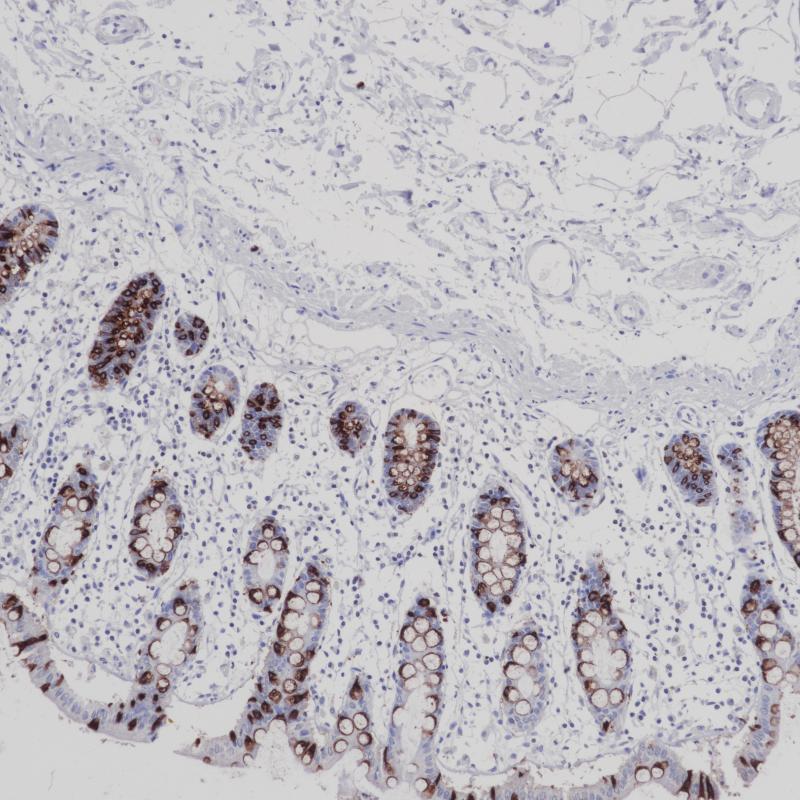

MHC II(DRα chain) 重组兔单克隆抗体

主要组织相容性复合体 II 类(MHC II 类)分子是在巨噬细胞、树突细胞和 B 细胞等抗原呈递细胞表面表达的异二聚体的跨膜糖蛋白。在人体中,MHC II 类蛋白复合体被人白细胞抗原基因复合体 (HLA) 编码。MHC II可在 B 淋巴细胞、活化的 T 淋巴细胞、活化的自然杀伤 (NK) 细胞等表达。

阳性对照

食管